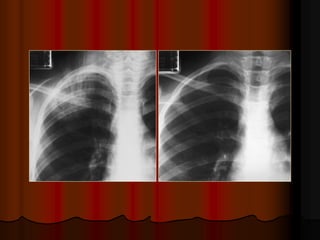

 Phim phaûi ñöôïc chuïp ôû tö theá thaät ngay

thaúng: Khoaûng caùch töø ñaàu trong xöông

ñoøn hai beân ñeán maáu gai ñoát soáng baèng

nhau (ñoái vôùi treû em thì so saùnh khoaûng

caùch töø ñaàu trong cung söôøn tröôùc ñeán

ñöôøng giöõa).

Được xem là cân đối khi khoảng cách từ đầu trong của xương

đòn hai bên đến gai sống bằng nhau.